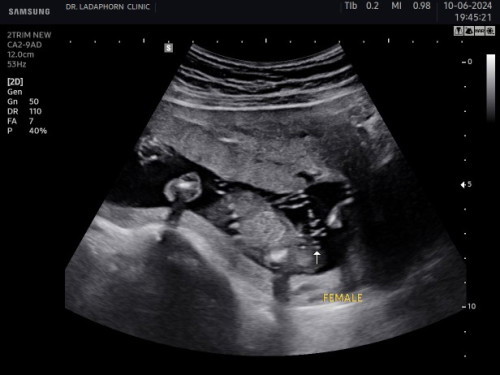

สอบถามแม่ๆธีมลูกสาวหน่อยคะ

ตรงลูกศรชี้ คือกลีบ ใช่มั้ยคะ แม่จะได้ซื้อของรอ555

ลังเลเหมือนกันค่ะไปซาวด์มาล่าสุด55555 กลัวมีหน่อออกมา😂

แม่กลัวฟูเป็นใข่ เลยถามให้แน่ใจ555